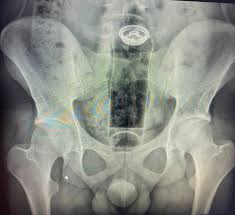

Um jovem de 19 anos precisou ser internado após introduzir um frasco de desodorante no ânus e o objeto ficar preso no reto. O caso foi relatado pelo cirurgião coloproctologista Daniel Brosco, que utilizou as redes sociais nesta segunda-feira (26) para fazer um alerta sobre os perigos da introdução de objetos inadequados para a prática sexual. Segundo o especialista, o paciente relatou que o incidente ocorreu durante uma “brincadeira” sexual. A embalagem acabou subindo para o reto e, após tentativas frustradas de retirá-la em casa, o jovem buscou ajuda médica.

O médico explicou que o intestino possui movimentos peristálticos (contrações involuntárias) que, somados ao vácuo criado na região, podem “sugar” o objeto, dificultando sua remoção manual.